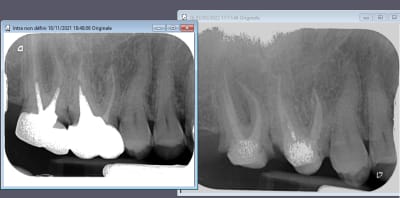

Retraitement de 17 et 16 en 2 temps.

La 17 retraitée en janvier présentait un canal MV en lame de couteau, comme décrit plus haut. La radio n'était pas si affolante que ça quant à la qualité du précédent traitement, et pourtant j'ai sorti des kilos de merde du canal.

La 16 présentait un MV2 distinct, non traité, mais qui ne semblait pas "visuellement" infecté.